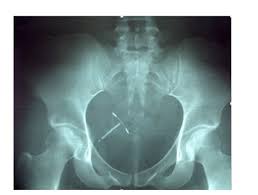

Modifier 53 Scenarios By Murriel And Cheryl Ppt Download from slideplayer.com Can i bill 58301 for iud removal and bill 58300 for iud insertion on the same day, if the provider removes and then inserts another iud? V25.02 z30.014 encounter for initial prescription of iud (not coded with the Same day iud removal and reinsertion when appropriate and supported by documentation, two cpt procedure codes, an e/m code, and a hcpcs supply code are reported for the one visit. The speculum was placed and the iud string visualized. This modifier is used when a procedure is started but discontinued and no other procedure is performed during the visit. These procedures are usually not done out of medical necessity; A modifier 51 (multiple procedures) is added to code 58300. To remove the iud, your doctor will grasp the threads of the iud with ring forceps.

Decoding Coding Office Hysteroscopy Newsscope from newsscope.aagl.org Can i bill 58301 for iud removal and bill 58300 for iud insertion on the same day, if the provider removes and then inserts another iud? Yes, there is no cci edit for those two codes. As for the e/m, it. 97.71 (removal of intrauterine contraceptive device) although some cpt codes are combination codes (e.g., code 11983 for a subcutaneous drug delivery implant removed and reinserted at the same time) the cpt manual does not include a code that represents both an iud insertion and an iud removal performed on the same day. As the iud is pulled out of the uterus, the flexible arms fold. Using ringed forceps, the iud string was grasped and the device was removed without difficulty. The health care professional evaluates the uterus and the position of the strings attached to the iud. To remove the iud, your doctor will grasp the threads of the iud with ring forceps.